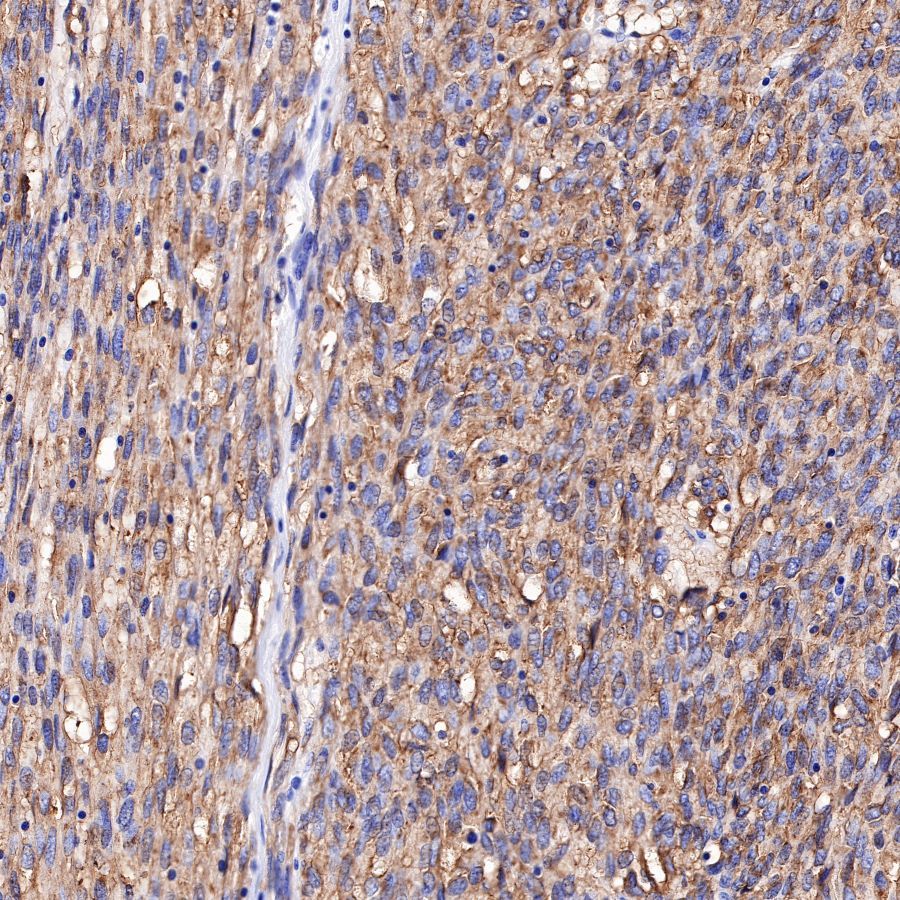

IHC shows positive staining in paraffin-embedded human chromophobe renal cell carcinoma.

Anti-CD117 antibody was used at 1/1000 dilution, followed by a Goat Anti-Rabbit IgG H&L (HRP) ready to use.

Counterstained with hematoxylin.

Heat mediated antigen retrieval with Tris/EDTA buffer pH9.0 was performed before commencing with IHC staining protocol.